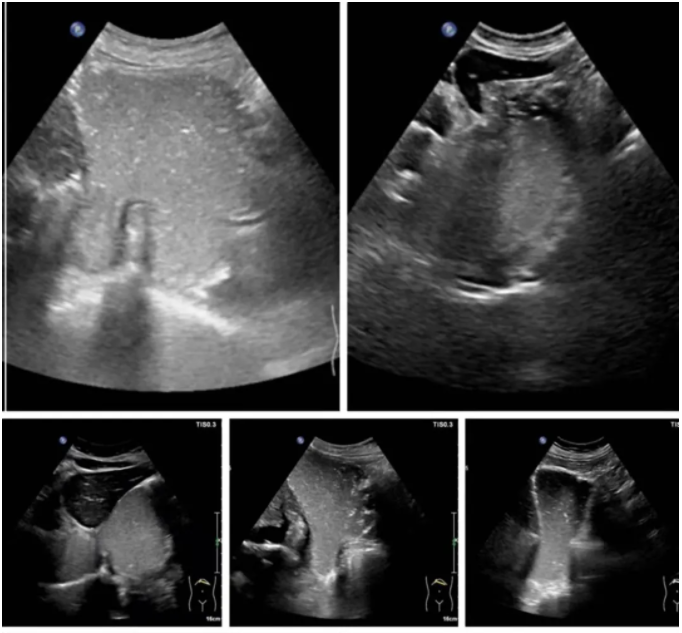

下图是不同表现的滑动型食管裂孔疝:宽窄不一的食管裂孔管径、大小不一的疝囊、或正常或变钝的HIS角,部分病例可见疝囊壁与胃壁回声及厚度一致的延续:

病例二,食管旁型食管裂孔疝:(图像来自于超声同仁提供,具体作者不详)

病例三,混合型食管裂孔疝,膈上两囊呈“双头征”: